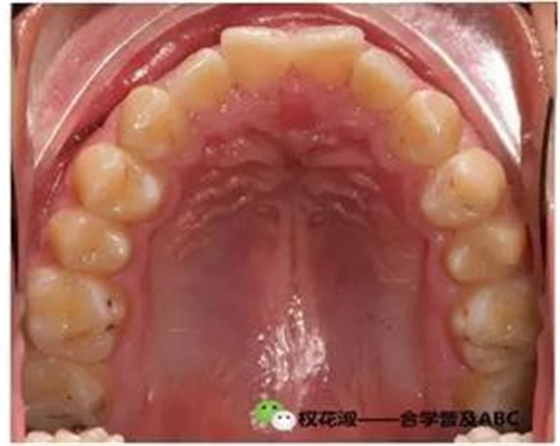

下面是理想合的幾張圖片:

大家在沒事的時候可以仔細(xì)琢磨這張幻燈,關(guān)于前后牙牙齒的覆合覆蓋,中線關(guān)系,牙齒的排列等等。其實這張幻燈對我們理解上下牙齒的咬合也是非常有幫幫助的。大家看右下的照片詮釋的是尖牙保護合的概念。

這張照片就是咬合的照片,也是讓大家加深牙齒形態(tài)完整性這方面的概念,也就是說如果想要保證穩(wěn)定的咬合關(guān)系,牙齒無磨耗是十分關(guān)鍵的。